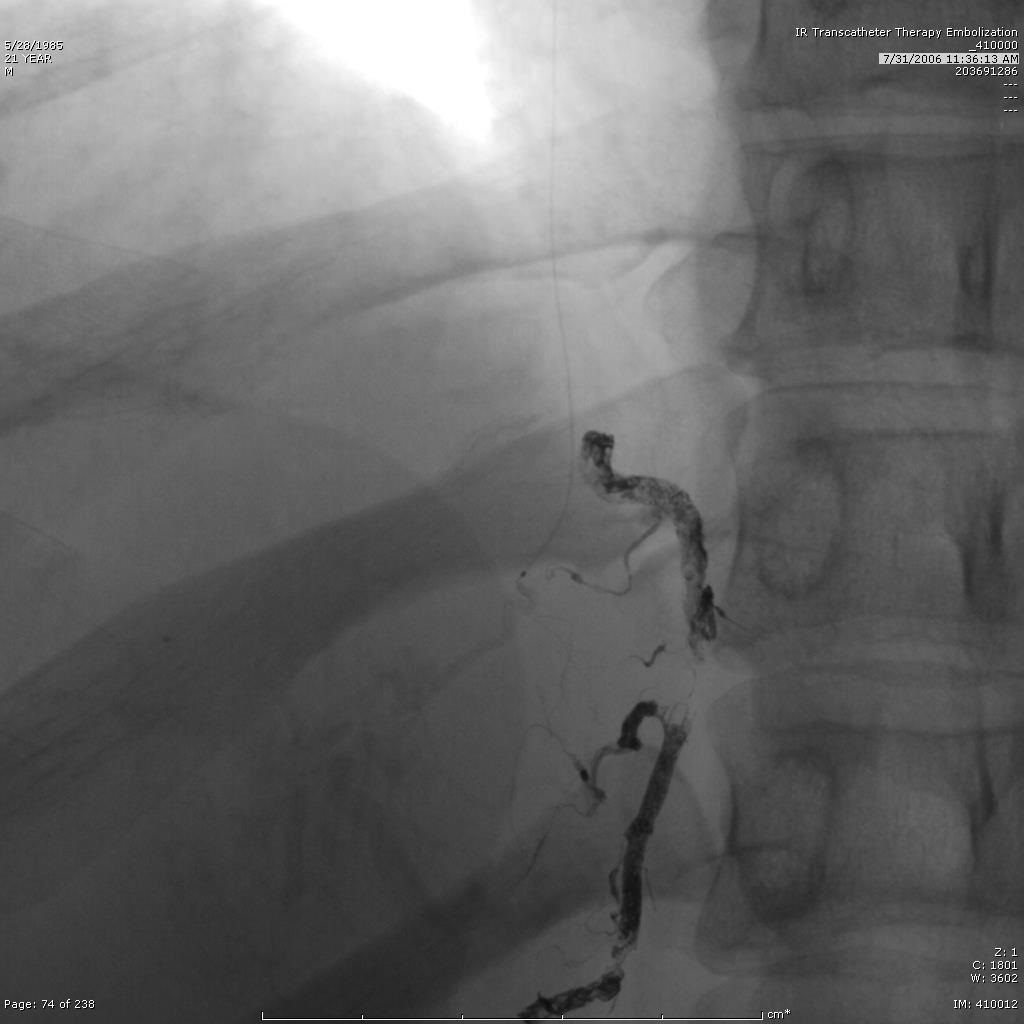

和血管内装置的联合应用可以使Onyx胶栓塞应用于高血流病变。包括使用球囊导管和在近端放置弹簧栓子以减慢血流再进行Onyx 胶的栓塞。 如果重要的正常动脉分支由血管畸形病变近端发出,如下图,脊髓前动脉由畸形的肺动静脉畸形发出。

在注射Onyx 胶之前,保护脊髓前动脉不被Onyx胶经逆向血流栓塞

Onyx 胶栓塞胃冠状静脉后意外肺动脉栓塞

Onyx 胶意外栓塞肺动脉